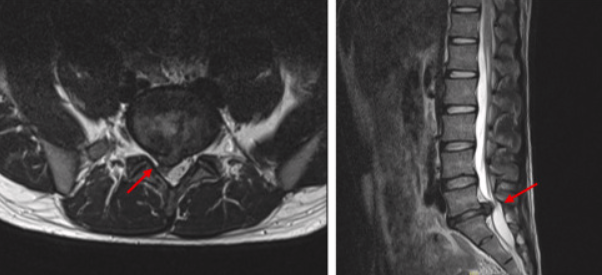

X-ray 검사를 통해 척추 간격 감소 여부를 확인합니다.

CT, MRI 등 영상검사를 통해 디스크 탈출의 위치와 정도를 정확히 평가합니다.

허리 디스크는 척추뼈 사이에서 주로 4-5 요추 사이, 5번 요추-1번 천추 사이에서 흔히 발생합니다.